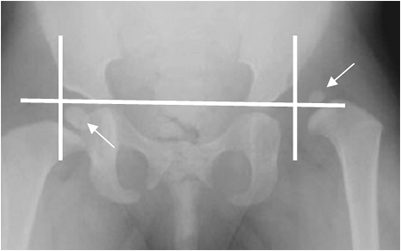

La Rx simple se utiliza para continuar el seguimiento. (2). Se encuentra disminución del ángulo de cubrimiento lateral, menor de 16º. (6). (Fig 35).

Igualmente hay desplazamiento laterosuperior del núcleo de crecimiento de la cabeza femoral. (2). Se traza una línea que pase por los cartílagos tri-radiados y otra vertical

que cruce por el borde lateral del acetábulo. La cadera queda dividida en 4 cuadrantes y el núcleo de crecimiento normal, se localiza en el inferointerno. (2). (Fig 36).

Fig 35. Displasia de cadera.

Rx AP. Angulo de cubrimiento acetabular negativo, por displasia.

Fig 36. Displasia de cadera.

Rx AP. Desplazamiento superolateral del núcleo de crecimiento izquierdo, por displasia. Núcleo de crecimiento derecho, de localización normal.